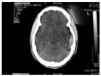

Hombre de 18 años que sufrió un accidente de moto mientras circulaba sin casco. Al ingreso hospitalario presentaba un GCS de 6. Se intubó y fue conectado a ventilación mecánica. La serie radiológica completa y la ecografía abdominal descartaron lesiones extraneurológicas. La TAC de cráneo mostró una línea de fractura temporoparietal izquierda, con hematoma epidural por debajo de la línea de fractura y varios focos contusivos intraparenquimatosos, sin desplazamiento de la línea media (grado 1b de la clasificación de Gennarelli) (fig. 1). La analítica sanguínea inicial no mostró alteraciones. Se practicó una craniectomía parietotemporal izquierda urgente para evacuación del hematoma epidural y se colocó un sensor intraparenquimatoso para medida de la presión intracraneal (PIC). Los primeros días presentó hipertensión intracraneal y requirió tratamiento con pentotal, manitol y diuréticos para controlar la presión intracraneal. En la TAC y la resonancia magnética (RM), realizadas en el control evolutivo, no se objetivaron nuevas lesiones. A partir del quinto día, ya sin pentotal, presentó tres o más episodios diarios de más de una hora de duración si no eran tratados, consistentes en hipertensión arterial, sudoración profusa, taquipnea, taquicardia, postura de descerebración y dilatación de ambas pupilas, que cedían con morfina intravenosa administrada en bolos. Estas crisis se manifestaron en presencia de tratamiento con infusión intravenosa continua de midazolam y retrasaron la suspensión de la sedación. Se intentó tratamiento profiláctico de las crisis con clonidina intravenosa administrada cada 6 horas, sin éxito. A partir del décimo día, ya sin sedación, el paciente mostraba un GSC 11-12, hemiparesia derecha y afasia de predominio motor. El día décimoquinto fue extubado y al alta, tras 19 días de estancia en la Unidad de Cuidados Intensivos (UCI) seguía presentando un GSC similar, así como los episodios referidos con frecuencia igual o superior a tres diarios, sin relación con estímulo externo, fiebre, infección u otra complicación. A los seis meses del traumatismo mostraba un grado 5 de recuperación según la escala Glasgow Outcome Scale (GOS) y los episodios citados habían desaparecido sin tratamiento específico alguno.

Figura 1. Tomografía axial computarizada (TAC) de cráneo al ingreso en el hospital. Imagen de hiperdensidad en región parieto-temporal izquierda compatible con hematoma extradural, con varios focos contusivos intraparenqimatosos subyacentes englobados en un área heterogénea de hipodensidad compatible con edema, sin llegar a desplazar línea media (grado 1b de la clasificación de Gennarelli).